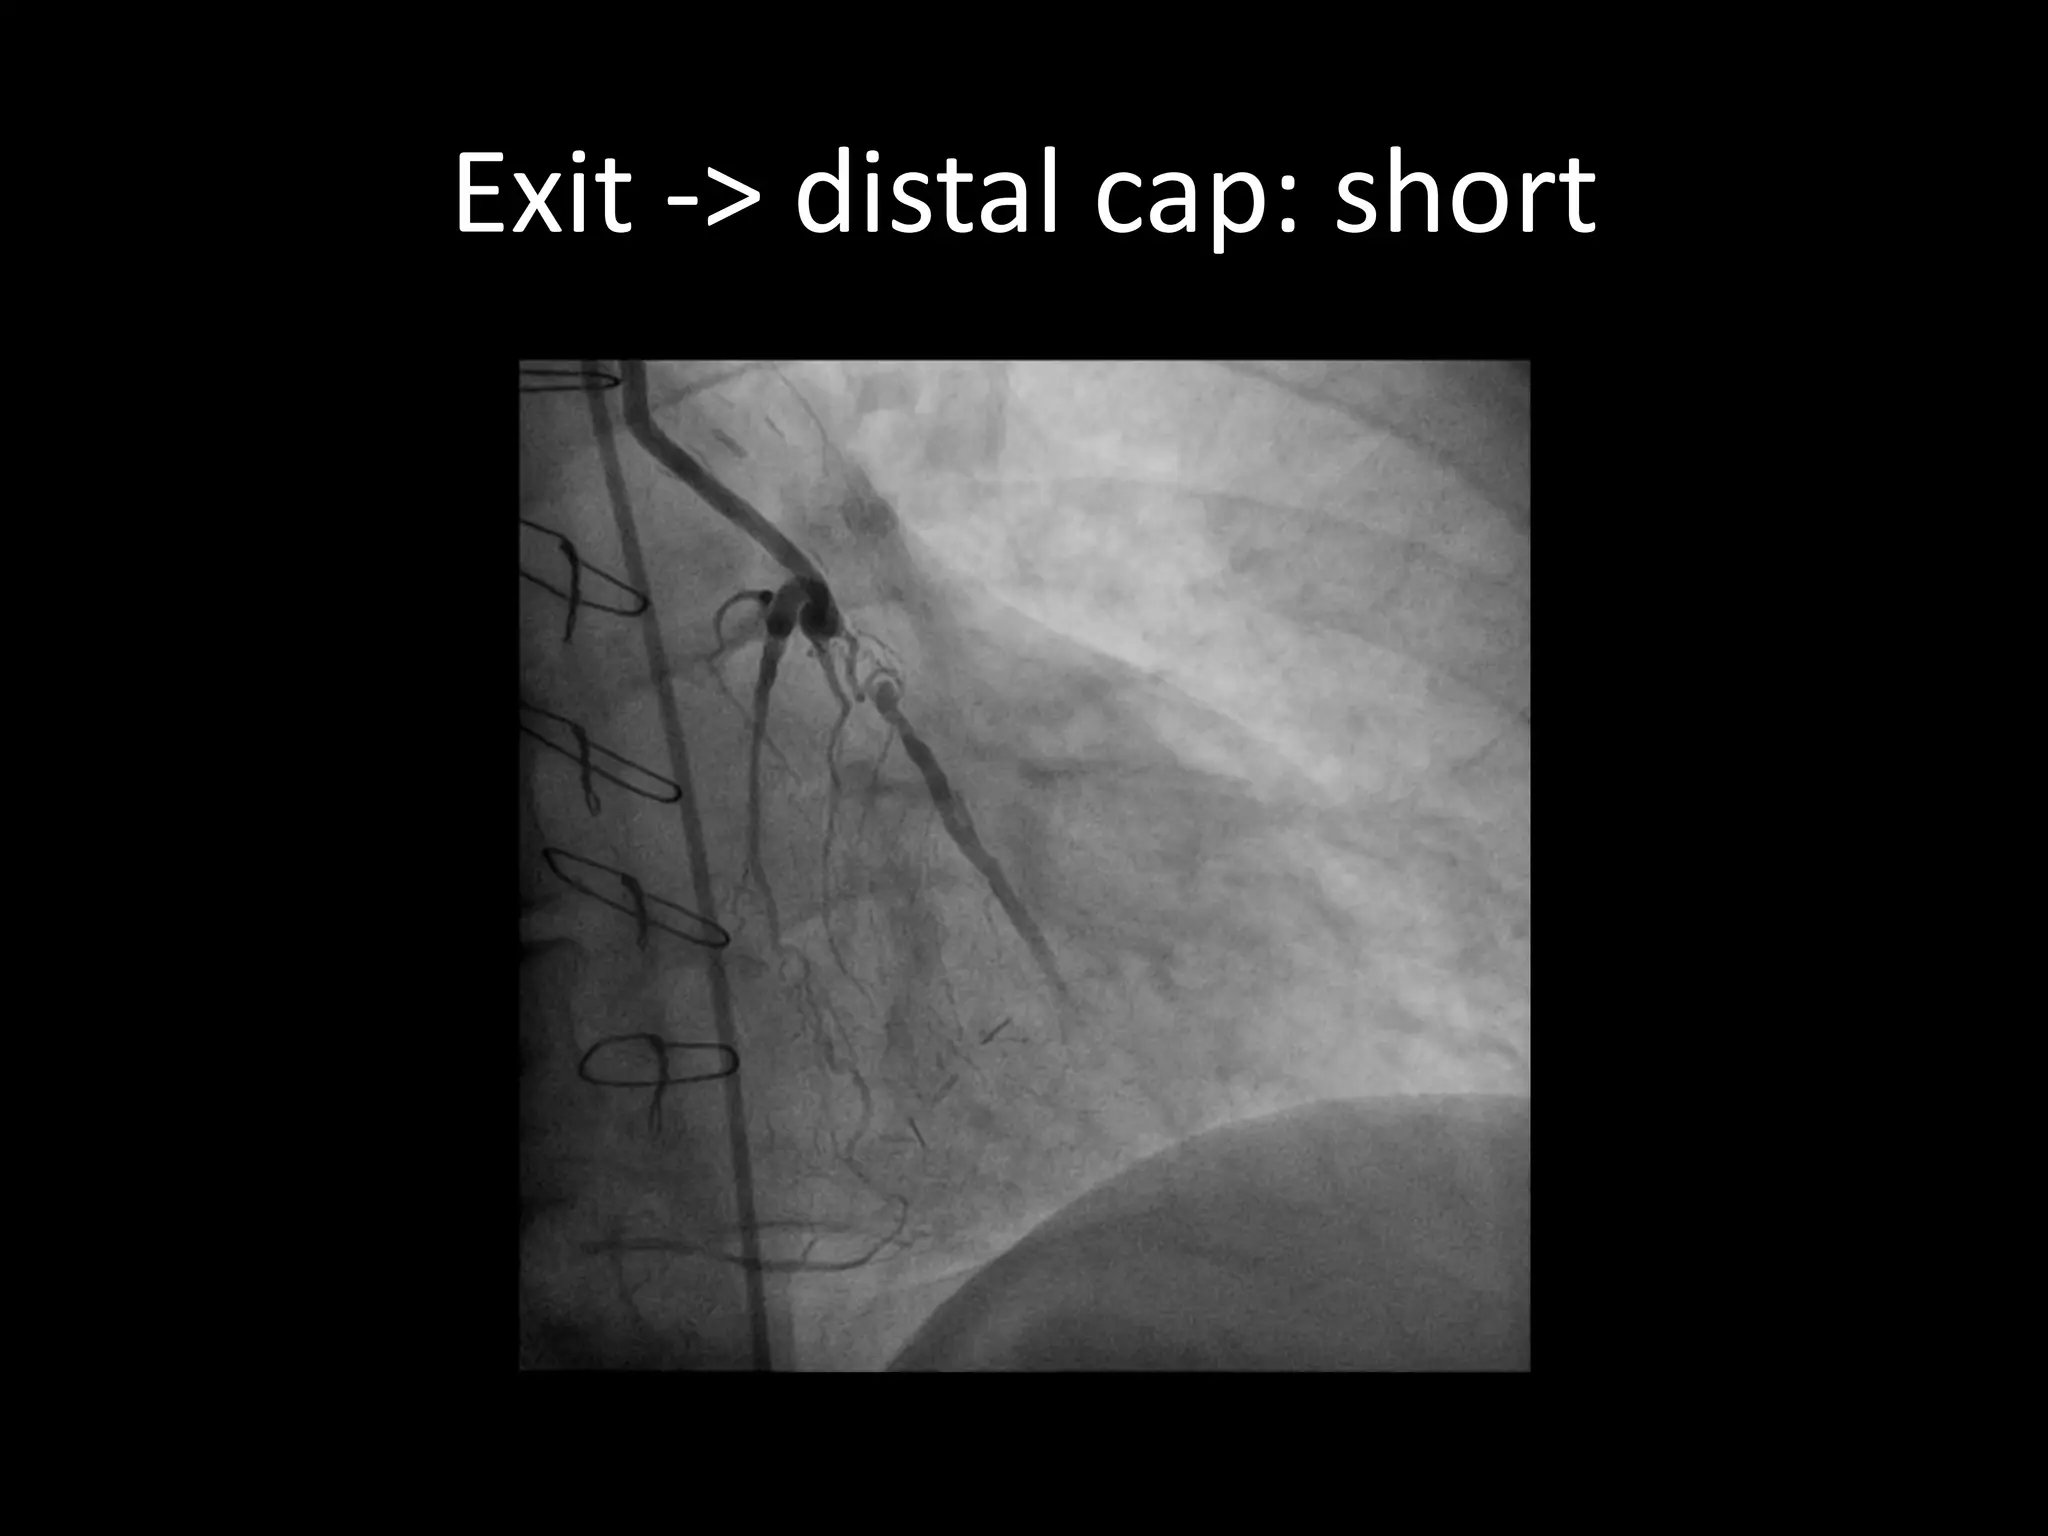

This document provides guidance on evaluating the feasibility of percutaneous coronary intervention (PCI) for a chronic total occlusion (CTO). Key factors to consider include: the patient's tolerance for a long procedure, contrast load, and radiation exposure; the CTO's proximal cap ambiguity, length, distal landing zone, and presence of interventional collaterals; and ensuring good quality angiography. With adequate planning and use of appropriate CTO techniques, feasibility is nearly always present for symptomatic patients. Success rates of CTO-PCI are reported to be 94% when using a planned approach.